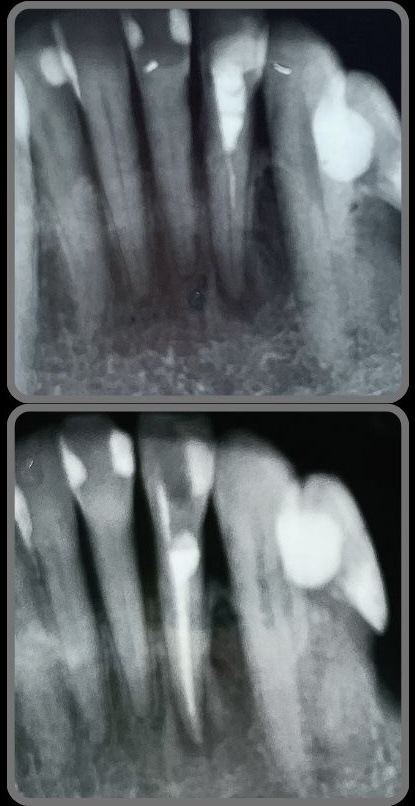

Veja alguns casos de sucesso